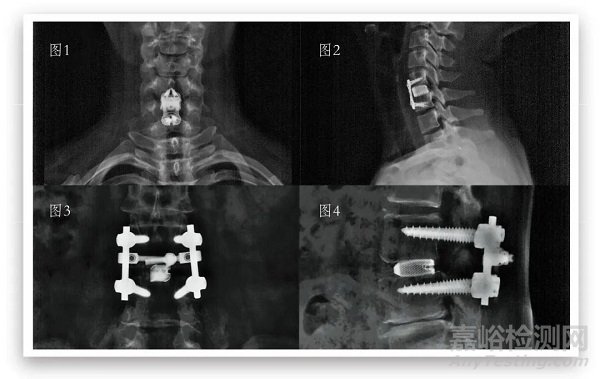

圖1:頸椎術后6月—正位 圖2:頸椎術后6月—側位

圖3:腰椎術后6月—正位 圖4:腰椎術后6月—側位